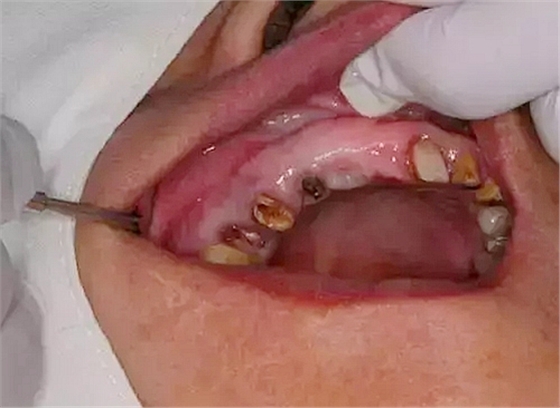

處理:14、15微創(chuàng)拔牙+拔牙位點保存術(shù)。

?患者口腔內(nèi)部情況